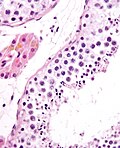

Image:

Micrograph of an epididymis. H&E stain.